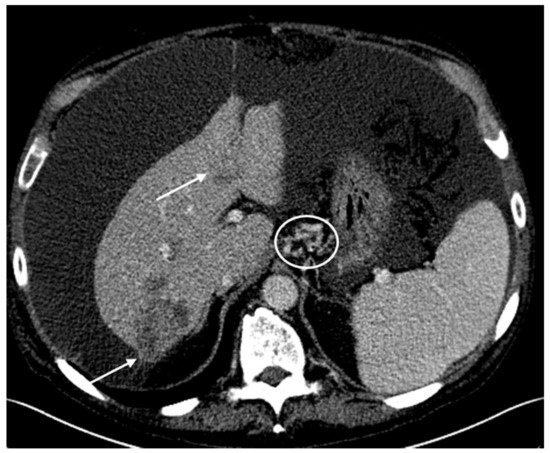

2.1. Patient #1

2.2. Patient #2